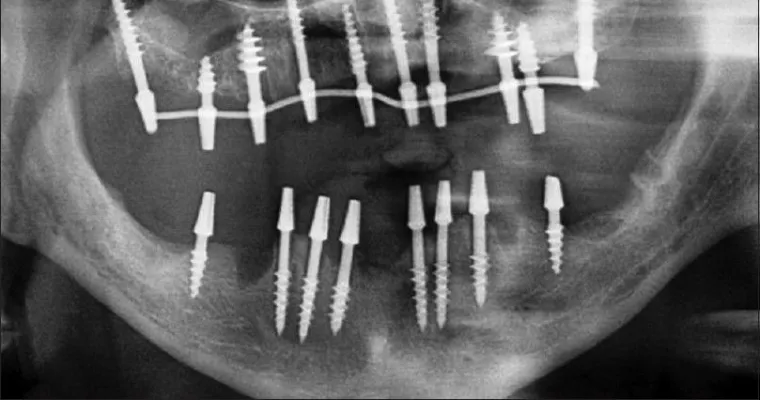

- Implantation stage: placing the basal implant in the upper and lower jaws and upper jaws as part two-stage implant placement of a control procedure. leveling and securing the basal dental implants to their correct position within the tooth arc.

Leveling and straightening of Implants, taking an impression of the upper and lower jaw